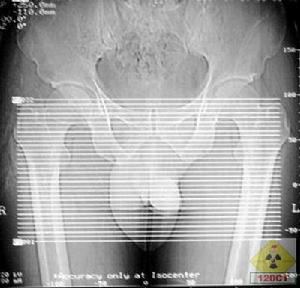

產生。 2、陰囊溫度升高:精索靜脈曲張後,因精索靜脈內血流郁滯,會使陰囊內...功能障礙:因陰囊內局部溫度升高、睪丸的供血和供氧不充足,勢必會影響睪丸曲細...:研究表明,當出現精索靜脈曲張時,睪丸組織內氧自由基增加,脂質過氧化作用...